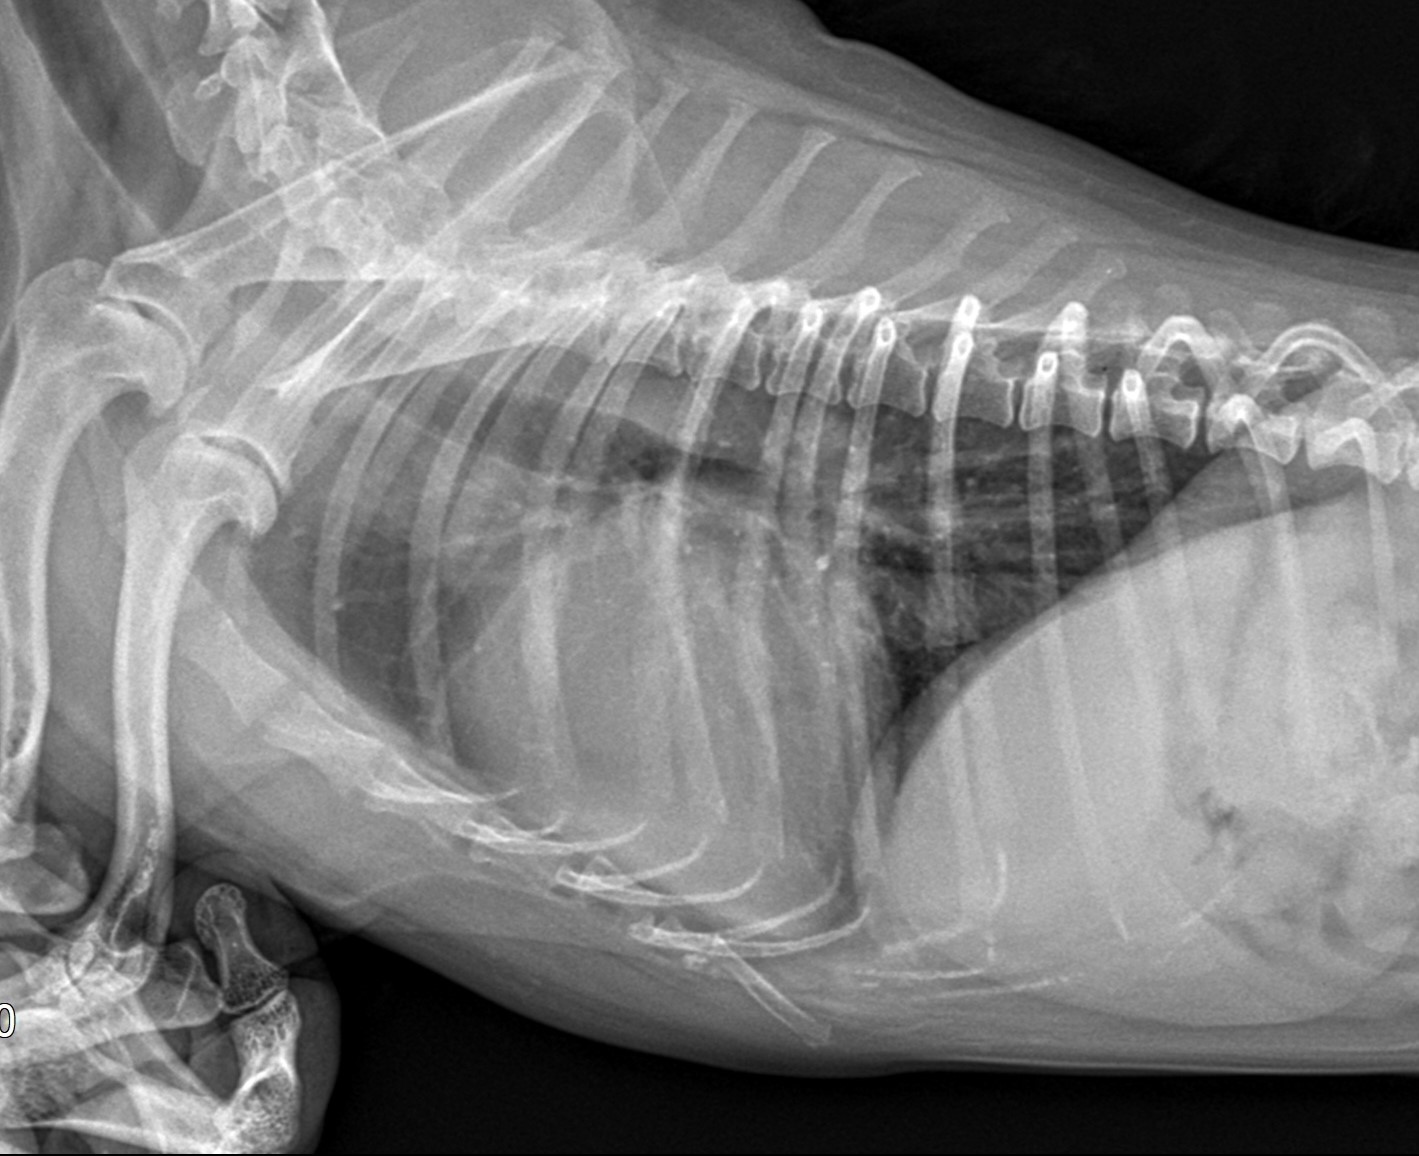

- 심장병이 진행되면 식욕이 줄고 근육량도 감소하여 체중이 급격히 줄 수 있다. 또한 복부에 물이 차는 경우도 있으며, 이로 인해 배가 불룩하게 나올 수 있다.

- 강아지가 평소보다 자주 기침하거나, 누워 있을 때 특히 기침을 심하게 하는 경우가 많다. 또한 운동 후 호흡이 빨라지거나, 쉬고 있어도 헐떡이는 경우는 심장 기능 저하로 인해 폐에 수분이 차기 시작했음을 의미할 수 있다.

강아지가 평소보다 자주 기침하거나, 누워 있을 때 특히 기침을 심하게 하는 경우가 많다. 또한 운동 후 호흡이 빨라지거나, 쉬고 있어도 헐떡이는 경우는 심장 기능 저하로 인해 폐에 수분이 차기 시작했음을 의미할 수 있다.

심장병이 진행되면 식욕이 줄고 근육량도 감소하여 체중이 급격히 줄 수 있다. 또한 복부에 물이 차는 경우도 있으며, 이로 인해 배가 불룩하게 나올 수 있다.